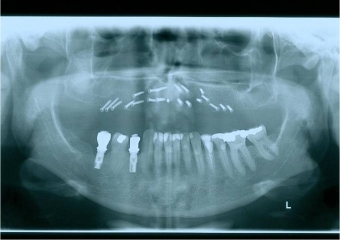

Raio x inicial